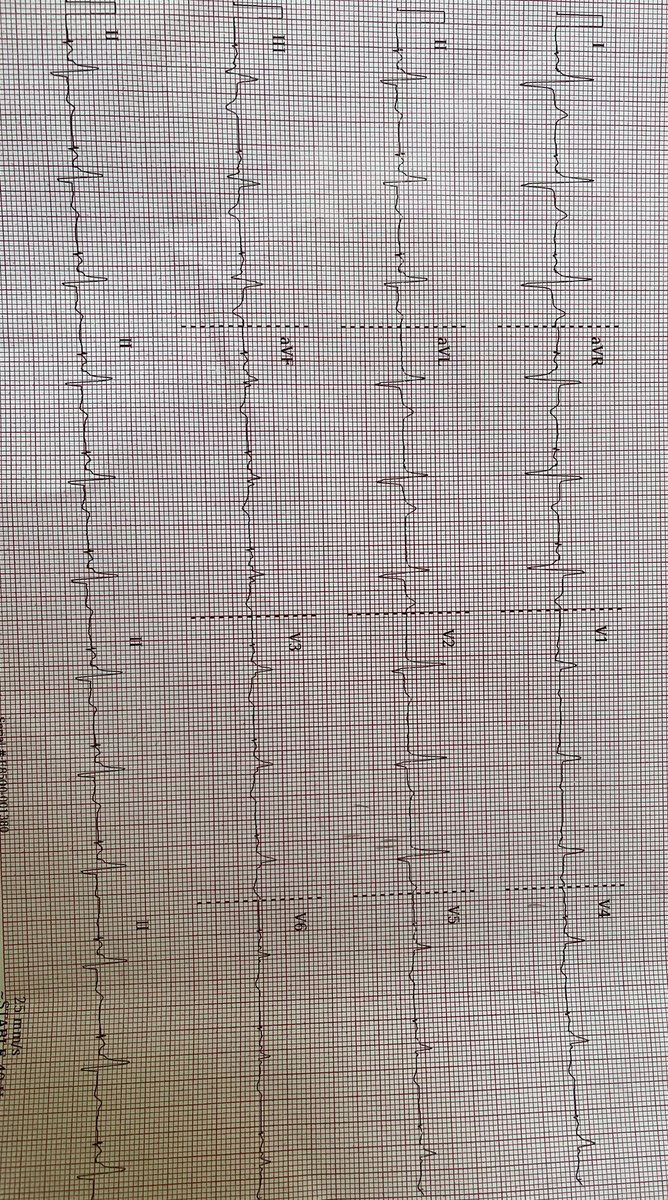

What’s happening? EP fellows chime in Faisal Merchant Mikhael El-Chami Alex Turin Amole Ojo AFPanico JMC Kalyanam Shivkumar MD PhD Roderick Tung Amin Al-Ahmad, MD Sergio Pinski Gregory Michaud Anand #EPeeps